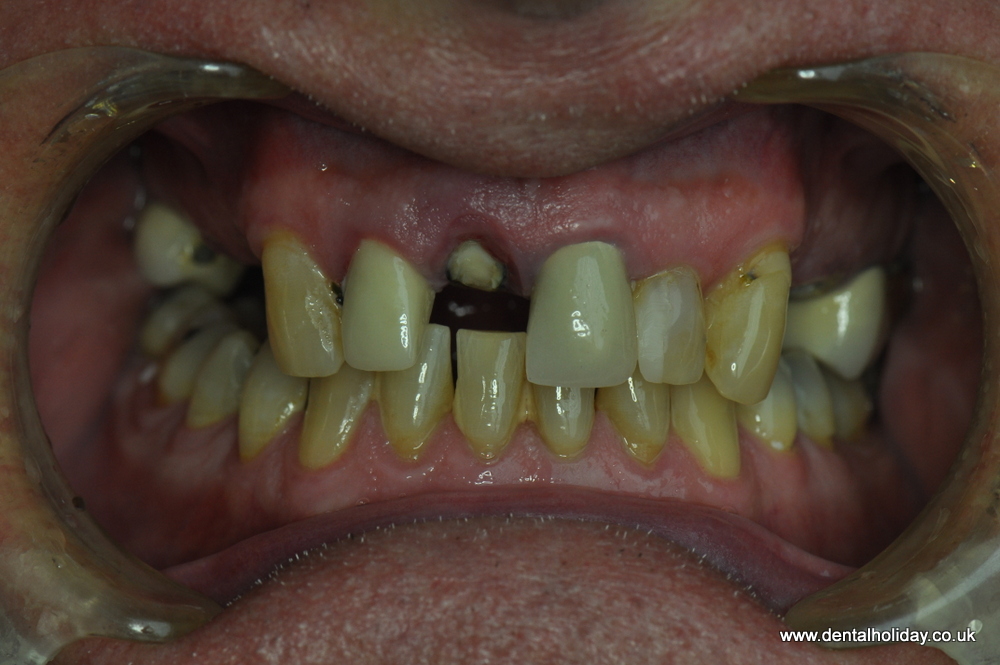

John was referred to us by his lovely sister, who recently had her dental treatment successfully completed with us in 2015. John had just a few missing teeth, but he noticed that existing teeth were breaking up over the past 12 months. He was therefore looking for a permanent solution, one that would last the rest of his days without having to visit the local dentist for continual repairs.

After his initial dental consultation done on the day of his 1st visit to us, our implantologist Dr. Marek prepared a personalized treatment plan for John, which included a 12 unit ceramic bridge fitted on 5 dental implants.

See the immediate change after first visit.